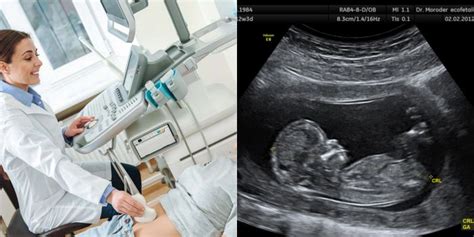

- Ultragarsas - instrumentinis tyrimas, kuris atliekamas naudojant aukšto dažnio garso bangas, siekiant ištirti krūtis. Atliekant krūtų ultragarsinį tyrimą, moteris guli ant nugaros, jos krūtis tiriama specialiu ultragarsinės įrangos jutikliu.